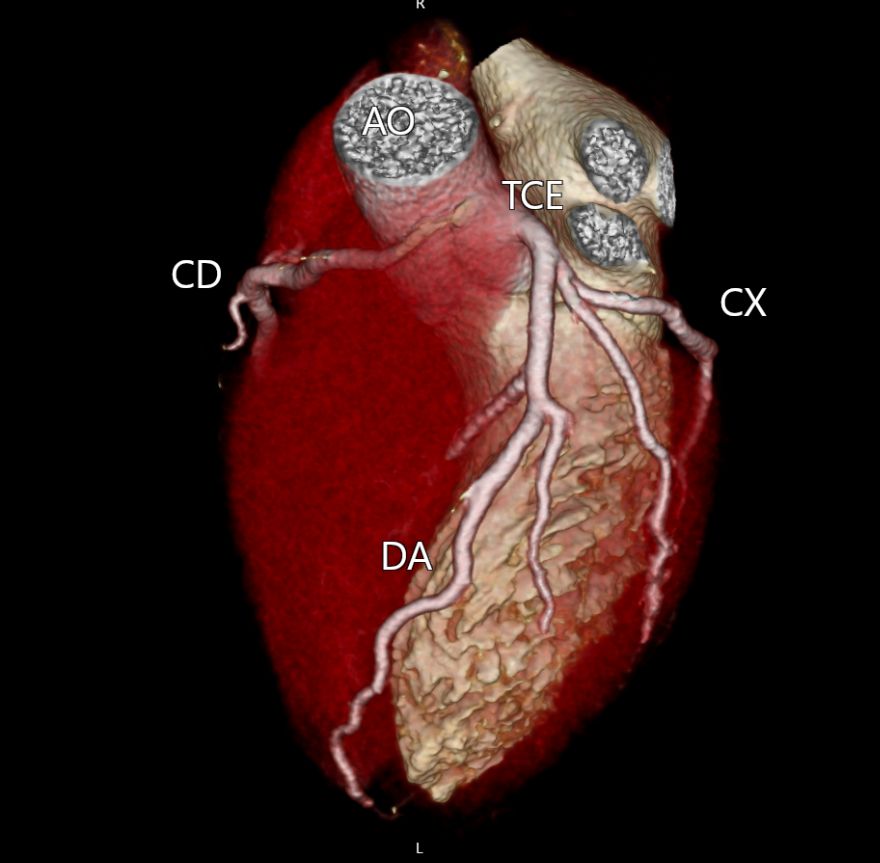

A angioTC de coronárias (CCTA) vem ganhando protagonismo na prevenção primária porque vai além do escore de cálcio: ela identifica placas não calcificadas, muitas vezes invisíveis ao CAC, e que podem representar aterosclerose ativa e risco real mesmo em pessoas classificadas como “baixo risco” pelos escores tradicionais.

Um grande estudo populacional recente (JAMA), com quase 25 mil indivíduos de 50 a 64 anos sem doença cardiovascular conhecida e seguimento de aproximadamente 8 anos, mostrou que a presença de placa não calcificada na CCTA se associou a maior risco de primeiro evento coronário e que a inclusão dessas informações anatômicas melhorou a predição de risco e a reclassificação, principalmente entre os pacientes inicialmente rotulados como baixo risco.

Na prática, isso muda o jogo: detectar precocemente placas não calcificadas permite “antecipar” o diagnóstico da doença coronária, individualizar a prevenção e orientar medidas mais assertivas — especialmente em pacientes que, pelo cálcio ou pelo risco clínico, poderiam ser falsamente tranquilizados.